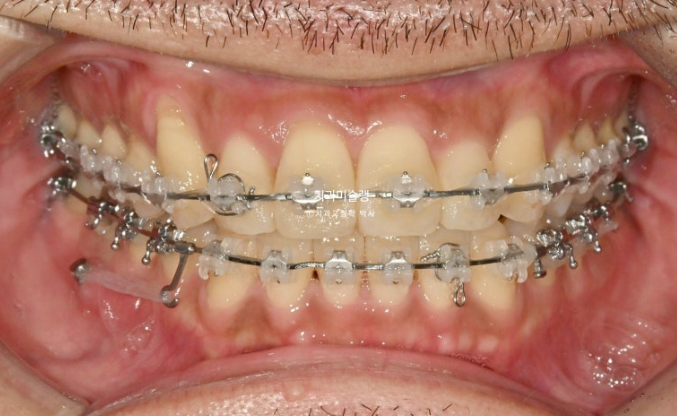

덧니가 있고 위아래 치아 중심선이 어긋나 있습니다.

치아중심선이 어긋나 있는 것은 아래턱 비대칭이 있기 때문입니다.

그에 비해 뒤쪽 어금니 교합은 좋은 편 입니다.

그 사이 윗니에 먼저 장치를 붙여 배열을 시작하고

24.12

2달 후 아랫니에도 장치를 붙여서 본격적인 교정을 시작합니다.

치료를 이어가다가 아래턱 비대칭에 의한 중심선 어긋남을 하기 위해 아래쪽에 교정용 나사도 하나 심었습니다.